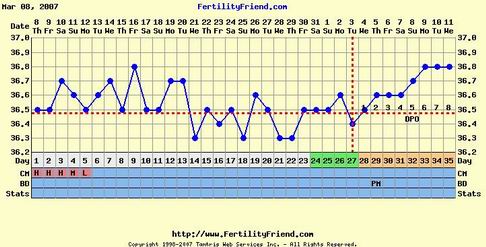

Hőd?!

Betette a ferty a pé-t?

Látom

Ez aztán a melegedés!!!Csak így tovább!!Ebből még bármi lehet!!